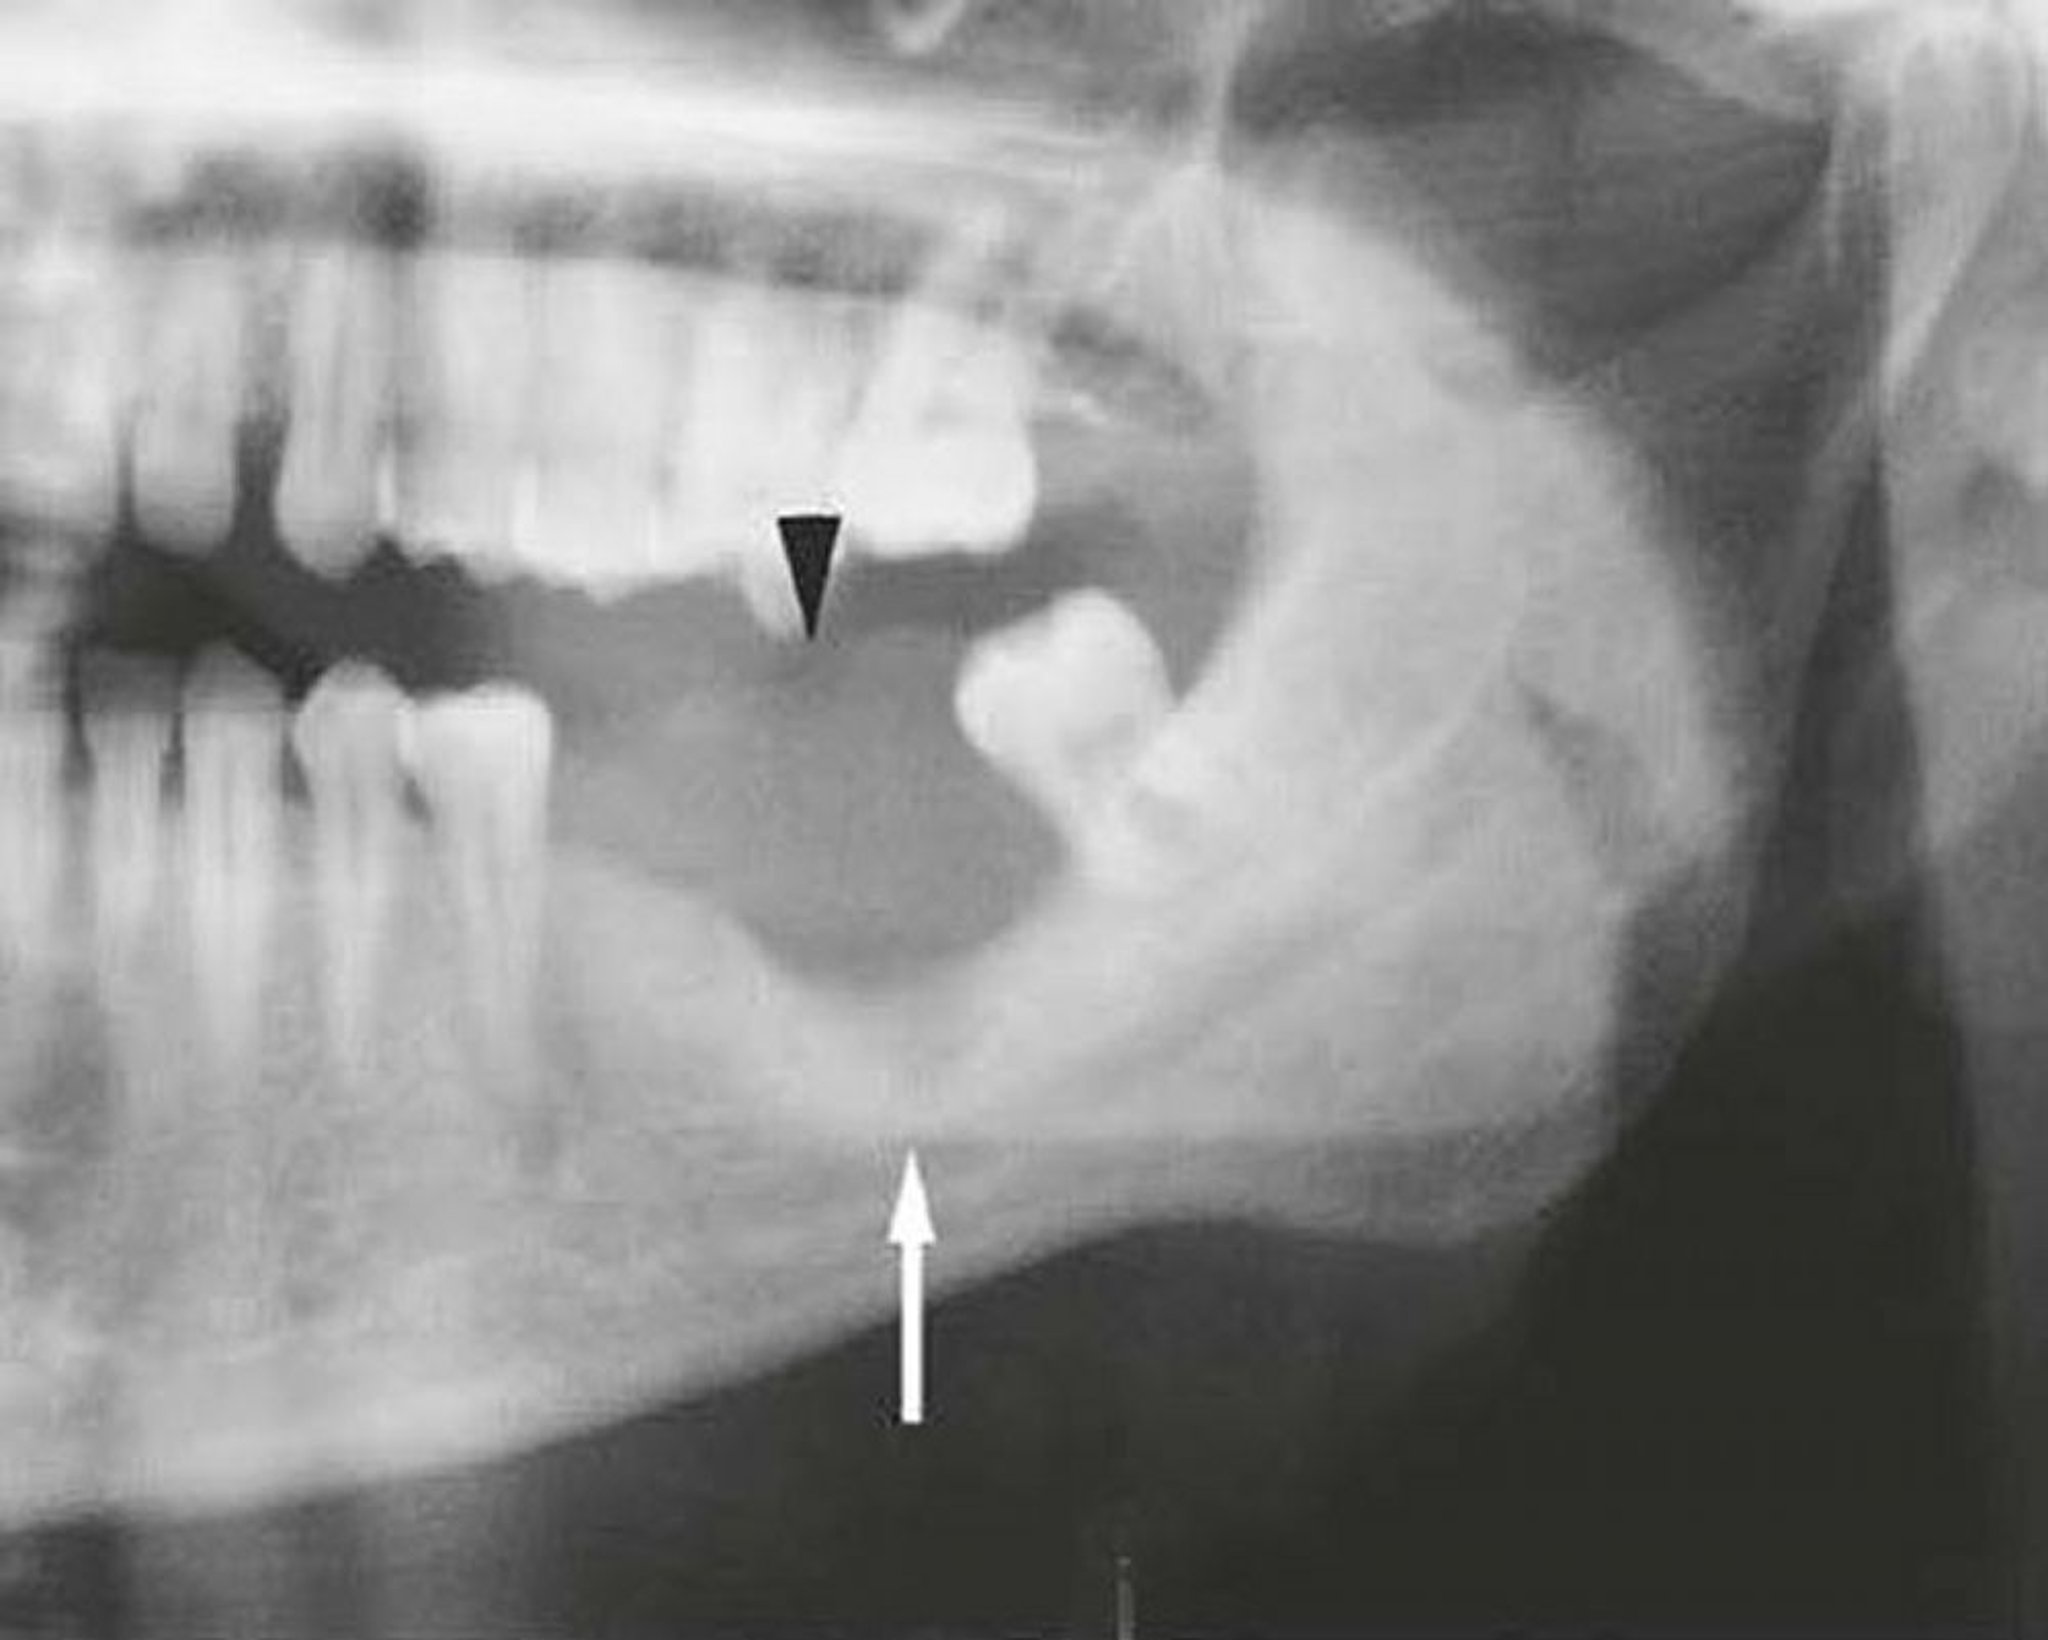

Carcinome malpighien de la mandibule

Cette image d'une mandibule envahie par un carcinome malpighien montre une masse des tissus mous (tête de flèche) et une destruction osseuse (flèche).